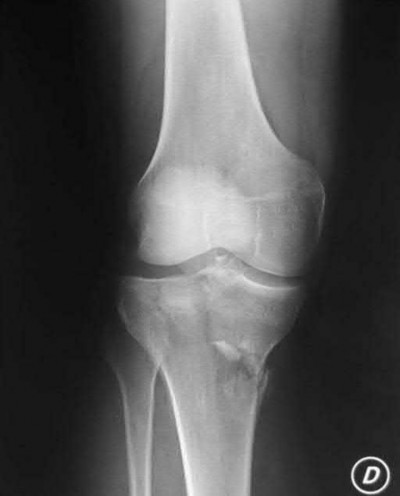

A 22-year-old male cyclist was struck by a car. He complains of right knee pain and swelling, as well as reduced sensation and weakness in his right foot. His leg compartments are soft and not tender. Distal pulses in the extremity are palpable. Radiographs of the knee, as shown in Figures A and B, were taken after a closed reduction maneuver was performed. What would be the next best step in management of this patient?

This patient presents with a Schatzker IV tibia plateau fracture with lower extremity neurologic deficits. The next best step would be to investigate for an acute vascular injury with ankle-brachial index measurements.

Fracture-dislocations of the knee must be suspected with all Schatzker type IV injuries as this fracture pattern is usually associated with high energy trauma. Identifying this injury should prompt a thorough assessment of the neurovascular structures across the knee. After closed reduction and emergent immobilization of the knee, ankle brachial indices (ABI) must be immediately performed. If

Knee dislocations are associated with popliteal artery injury in 18-45% of cases and range from intimal tears to complete transection. Amputation rates of 85% have been reported if revascularization is delayed greater than 6 to 8 hours.

Neurologic injury occurs in 15-40% of cases and is most common after posterolateral dislocation. The peroneal nerve is more commonly injured.

Rihn et al. reviewed the acutely dislocated knee. They recommend a vascular consult if pulses are weak, or ABI is compromised. They warn that in arterial injury, pulses, temperature and capillary refill can be normal. If the limb remains ischemic, surgical exploration and revascularization is indicated.

Medina et al. systematically reviewed neurovascular injury after knee dislocation in 862 patients. Vascular injury rate was 18%, and nerve injury rate was 25%. Repair was performed in 80% of vascular injuries, and amputation in 12%. The most vascular injury was seen in KDIIIL injuries (32%) and posterior dislocation (25%).

Figure A is an AP radiograph of a posterior knee dislocation. Figure B is a lateral showing the same injury.